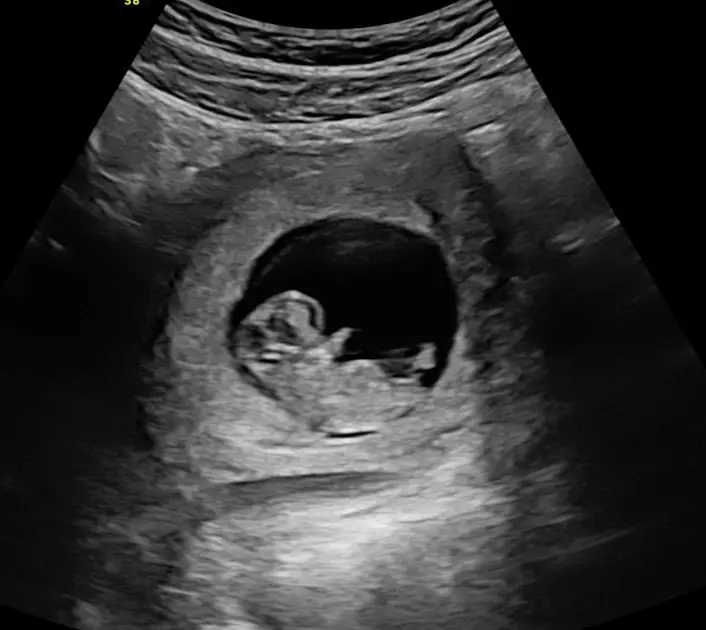

Whilst an early pregnancy ultrasound is not recommended for all pregnancies, we recognise it remains an important test for those with complications of early pregnancy, are unsure of their conception date, or just need extra support in these early days. It can help check the viability of your pregnancy, check the pregnancy is growing in the right place, and identify twins early.

The days of considering the 12 week ultrasound as just a screening test for chromosome abnormalities (like Down syndrome) are long gone. Advances in ultrasound technology mean that we can start to examine your baby’s anatomy much sooner than in the past. The first trimester anatomy scan is performed between 12 and 14 weeks gestation and is an important option to check the development of your baby no matter your choices for chromosomal screening.

With advances in ultrasound technology, your baby’s anatomy can be seen in great detail between 12 and 14 weeks gestation. It is now possible to see your baby’s arms, legs, fingers, and toes as well as skull, heart, brain, stomach, and kidneys.